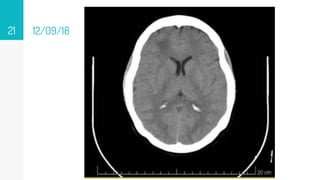

12/09/18

▹ 12/09/18

11/10/18

• #83 12 09 18 Area hipodensa en sustancia blaca subcotical en región frontal 20x17 mm 23-32 ud Onfl con dedema perilesional 11 10 18 imagen hipodensa digitiforme en rango 42- 47 Unid Onfil cortico-subcortical en lóbulo frontal derecho, 17.25 und Onfil lóbulo parietan e imagen en región occipital sin aumento de la amplitud de los ventrículos RM 30 10 18 se observan imágenes algunas hipodensas en secuencias T1, otras de señal intermedia muy heterogéneas, hipointensas en secuencias Flair y T2 con realce importante algunas en forma nodular, otras en forma periférica posterior a la administración de gadolinio, las de la región temporal derecha y occipital ipsilateral, con edema perilesional, mucho más importante en la de la región occipital, que debe correlacionarse con antecedente clínico reciente. En el Centro semioval en el lado izquierdo se observan pequeñas imágenes puntiformes hiperintensas en secuencias Flair y T2 pueden corresponder a lesiones vasculares isquémicas de pequeños vasos